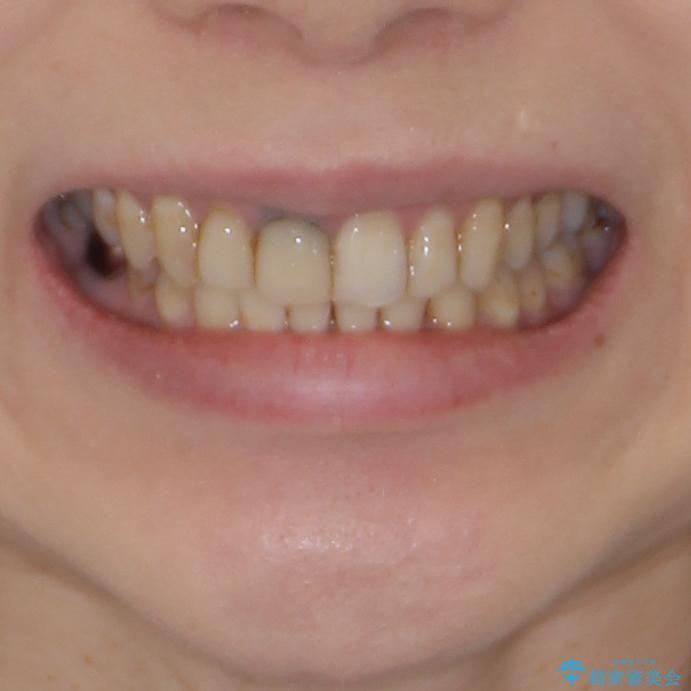

- 前歯の歯並びやむし歯治療の跡、奥歯の銀歯を気にして来院された患者様です。

インビザラインによる矯正治療の後に虫歯や銀歯をセラミックにて補綴することとしました。

前歯のむし歯治療の跡や奥歯の目立つ銀歯がなくなり、明るい口元になりました。